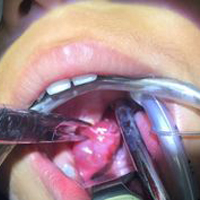

Если ваш ребенок слишком часто болеет ангинами, которые тяжело поддаются лечению антибиотиками, ваш доктор может предложить вам провести операцию по удалению миндалин (тонзилэктомию). Показанием к такой операции может быть следующее:

Операцию по удалению миндалин проводя также в том случае, если у ребенка возникли следующие осложнения:

- абсцесс, который не поддается лечению антибиотиками.

Тонзилэктомию проводят обычно в амбулаторных условиях, если только ваш ребенок не очень маленький, у него нет никаких других сложных заболеваний или если не возникает никаких осложнений во время проведения операции. Чаще всего ребенок может идти домой в тот же день, когда ему была проведена операция по удалению миндалин. Полное выздоровление наступает обычно спустя две недели.